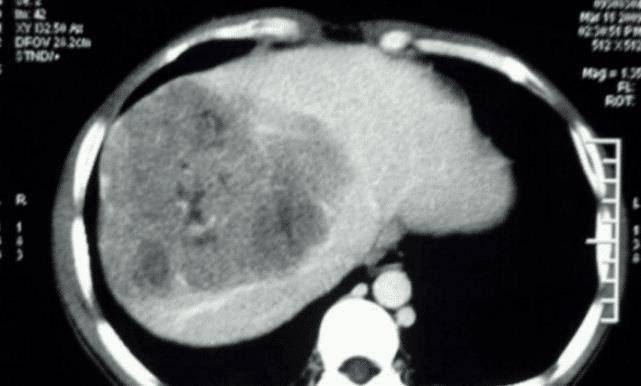

过了大概有一个月 , 楚潇潇的情况越来越严重 , 于是便来到医院检查 , 结果显示血清总蛋白70g/L , 且甲胎蛋白高达504ng/ml , 最终确诊为肝癌 。